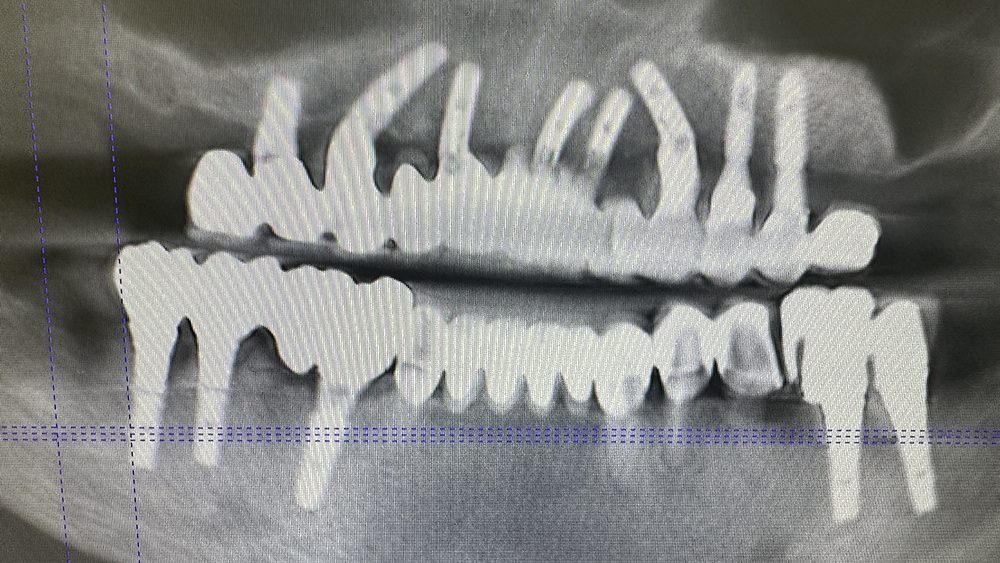

症例1

Before

After

非喫煙、碧南の陶芸家 70代男性

治療の期間・回数:①約7か月 ②約8か月 ③5か月

治療の価格:①2,200,000円 ②約8,000,000円 ③約300,000円

治療内容:この方は平成22年に初めて来院されました。

①他院で下あごの奥歯にインプラント治療を受けていましたが、上あごは「できない」と言われたそうです。当院では上あごに7本のインプラントを入れ、その日のうちに仮のブリッジを装着しました(即時荷重)。

②令和元年には、左上の奥のインプラントが抜けてしまったため、骨を足す手術(サイナスリフト)を行い、同時に2本のインプラントを追加しました。その半年後に、以前のブリッジを修理して再利用しています。

③さらに令和3年には右下の奥歯が折れてしまったため、インプラントを1本追加しました。当院では再治療や追加治療の場合、費用は2割引きとしています。

現在、上あごのブリッジは「コバルトクロム合金+セラミック」で作られた、スクリューでしっかり固定するタイプです。精度が高く、長く安定させるために、このような固定方法が望ましいと考えています。